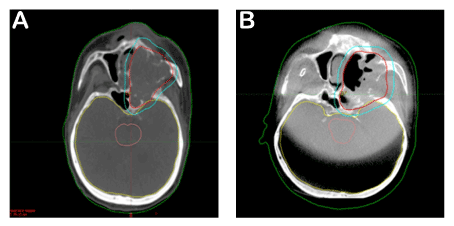

The treatment of the patient, who was at stage 4b in clinical staging and was regarded as non-operable, was planned as follows. As the sarcomatous component was a subtype of the squamatous cell tumor, it was decided to perform a definitive radiotherapy along with chemotherapy to be applied once every three weeks for its radiosensitive effect. Cisplatin was not used due to the deficiency in renal functions. Instead, carboplatin was used once every 21 days at 100 mg/m2/day. The left paranasal sinus region and the bilateral neck of the patient were identified as the target volume for radiotherapy. Intensity modulated radiotherapy technique was used and it was planned to perform 6572 cGy radiotherapy in 31 fractions. The patient underwent treatment every day with daily imaging. A regression at a rate of 1/3 was observed in the tumor in the weekly imaging (Figure 4).

Figure 4. CT images: This image shows tumor volume before treatment. Red line is surrounding of tumor area (A). Second image displays treatment effect of radioteraphy (B). Please compare to Figure-4A, note decrease of tumor volume